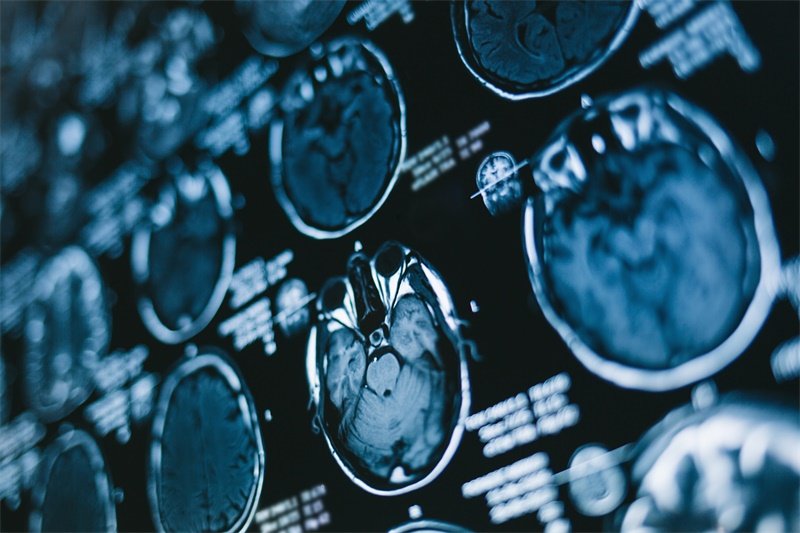

影像学检查

CT或MRI是最常用的影像学检查方式。这些成像技术能清晰显示囊肿的位置、大小及其对周围组织的影响。